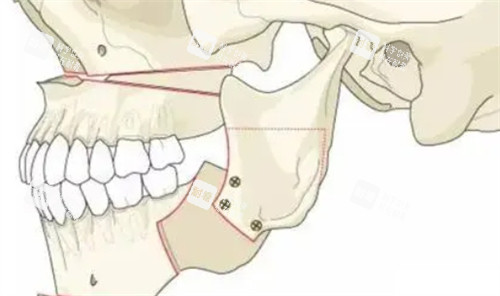

这些逆袭病例背后,是周会喜团队20年磨一剑的“硬核技术”。作为南方医学大学口腔颌面外科主管医师、广东省整形美容团队理事,他手里的“家伙事儿”可不止手术刀——CT影像+3D打印导板,能把颌骨截骨误差控制在0.1毫米内,“就像给骨头装了个GPS,避开神经血管,连‘歪嘴’都能精细复位!”

传统正颌手术要在脸上开外部切口,插引流管,术后肿得像“发面馒头”,改善期长达3个月。但周会喜团队用口内切口+超声电刀剥离组织,出血量不到传统手术的1/5,“术后不用插管,肿胀期缩短到1-2周,堪称‘午休式手术’!”更绝的是,他不仅修复咬合功能,还会根据五官比例设计颌骨形态——“月亮脸”求美者,他会增加下颌角宽度,告别“锥子脸违和感”;“大小脸”求美者,通过骨缝调整,让左右脸对称度堪比3D打印。